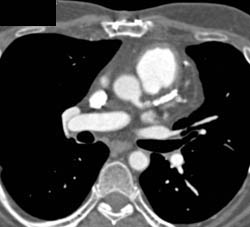

Pericardial Effusion